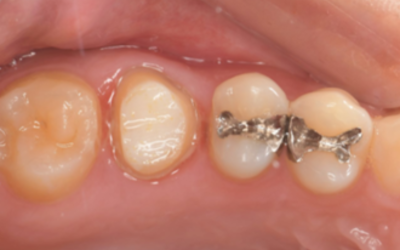

移植3ヶ月後の口腔内写真

移植3ヶ月後。

歯根周囲に透過像を認めるが動揺などはなく、歯周ポケットも形成されていなかった。

移植12ヶ月後の口腔内写真

移植12ヶ月後。セラミッククラウンで歯冠を修復した。

デンタルX線写真では透過像もほぼ消失している。